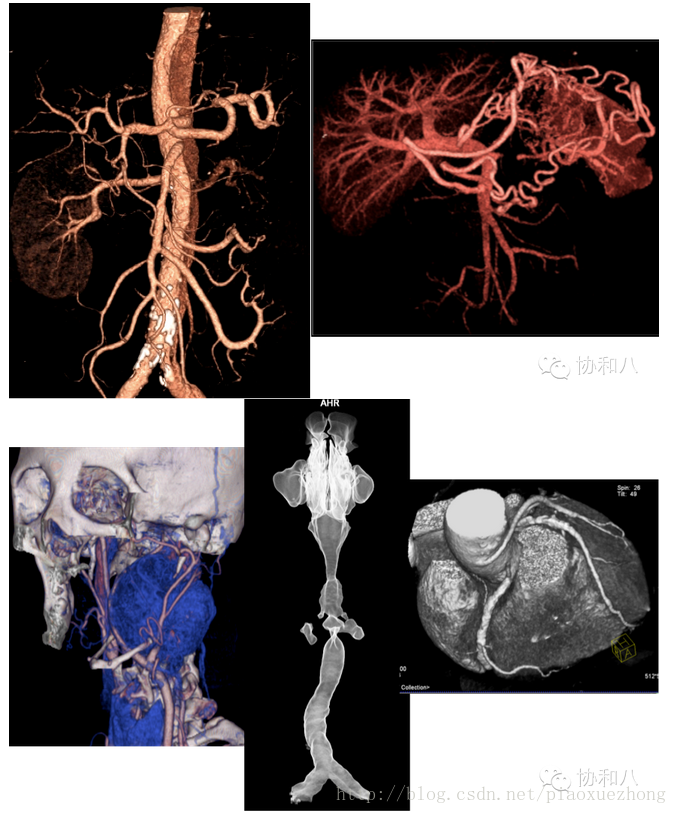

容积漫游技术(VRT)

这种三维成像功能非常强大,形态及色彩逼真,绝对是CT三维重建中的“高富帅”,可以对动静脉血管、软组织及骨结构等进行立体塑形成像,也可以显示支气管树、结肠及内耳等结构,对于复杂结构的成像有一定优势。

VRT图像直观生动,深受广大医生的喜爱,称得上是辅助诊断、显示病变的大杀器,但是我们要注意一点:VRT图像的伪彩设置很重要,不恰当的伪彩设置会将血管外层像素过滤掉,显示的血管狭窄的程度会比真实情况严重。